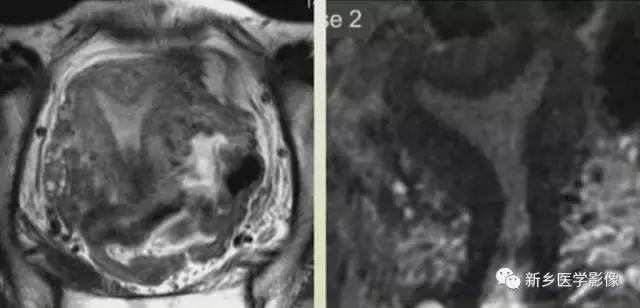

左图:完全纵隔子宫,纵隔延伸至宫颈内口。

中图:部分纵隔子宫,纵隔未达宫颈内口。

纵隔子宫:宫底轮廓凸出、平坦、轻度凹陷<1cm,肌壁或纵隔深入内膜腔>1cm。

弓形子宫:宫底轮廓凸出、平坦、轻度凹陷<1cm,肌壁或纵隔深入内膜腔<1cm。

完全型纵隔子宫:短T2信号纵隔贯穿宫腔,宫颈管及阴道上段。

MR诊断为完全型纵隔子宫伴阴道纵隔。

完全型纵隔子宫:宫底平坦,纵隔贯穿宫腔和宫颈

不完全型纵隔子宫:宫底平坦,纵隔未达宫颈内口水平